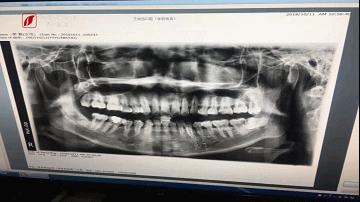

太原市的小樊吃嘛嘛都不香,原因是智齒太疼了,就想著找地兒把它拔了,可這過程并不順利。小樊說,自打她在艾尚齒口腔拔完牙的這段時間里,隨時隨地都在感受“咬牙切齒”,有時候嘴張不大,有時候嘴唇是麻的,有時候還會影響咀嚼、吞咽。

出現(xiàn)這樣的情況后,小樊就找到當時給她拔牙的大夫,一起去北京的專業(yè)醫(yī)院進行檢查,那里的專家說是拔牙時把神經(jīng)扯斷了,無法根治……

圖片

這可把小樊氣得夠嗆,找了醫(yī)調(diào)委,也找了律師,可事情遲遲沒解決。當時到底咋回事?帶著疑問,記者輾轉(zhuǎn)電話聯(lián)系到了當時給小樊拔牙的大夫。她說,目前,小樊想要恢復就需要做一些介入和外科手術(shù),但創(chuàng)傷可能會造成二次傷害。目前,雙方就此事的解決方案正在協(xié)商中……